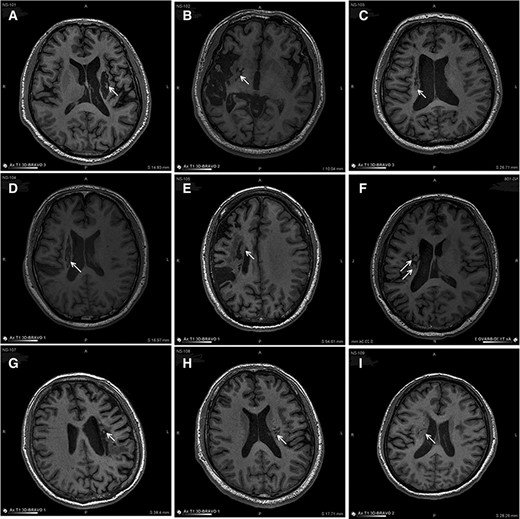

圖中顯示的是所有9名受試者(#101–109)在NSI-566移植后最新隨訪時的T1MRI圖像。箭頭指示梗塞腔位置。

(A):#101,24個月時,(B)#102,12個月時,(C)#103,14個月時,(D) #104,9個月時,(E)#105,14個月時,(F)#106,24個月時,(G) #107,21個月時,(H) #108,12個月時,(I) #109,14個月時。所有九個病例中梗塞腔內均有新組織生長。